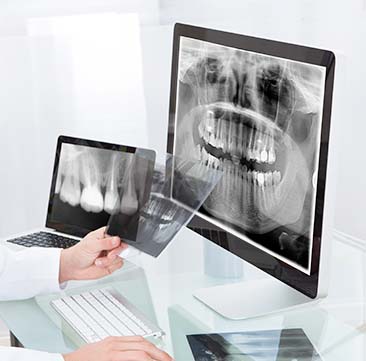

Special 01

실패 원인부터

과학적으로 진단합니다.

과거 수술 데이터 vs 현재 상태

오버레이 비교

3D CT 분석 및 정밀 진단으로

기존 수술의 실패 원인 파악

교합·호흡·저작 기능 회복을 위한

360도 시뮬레이션

• Procedure 01

상담 및 정밀 검사

1:1 맞춤 상담과 3D CT 촬영, 교합 분석 등

정밀 검사를 실시하여 문제점 진단

• Procedure 02

3D 시뮬레이션과 수술 계획 수립

3D 시뮬레이션, 원장님 정밀 상담 후

환자 맞춤형 수술 방향 결정